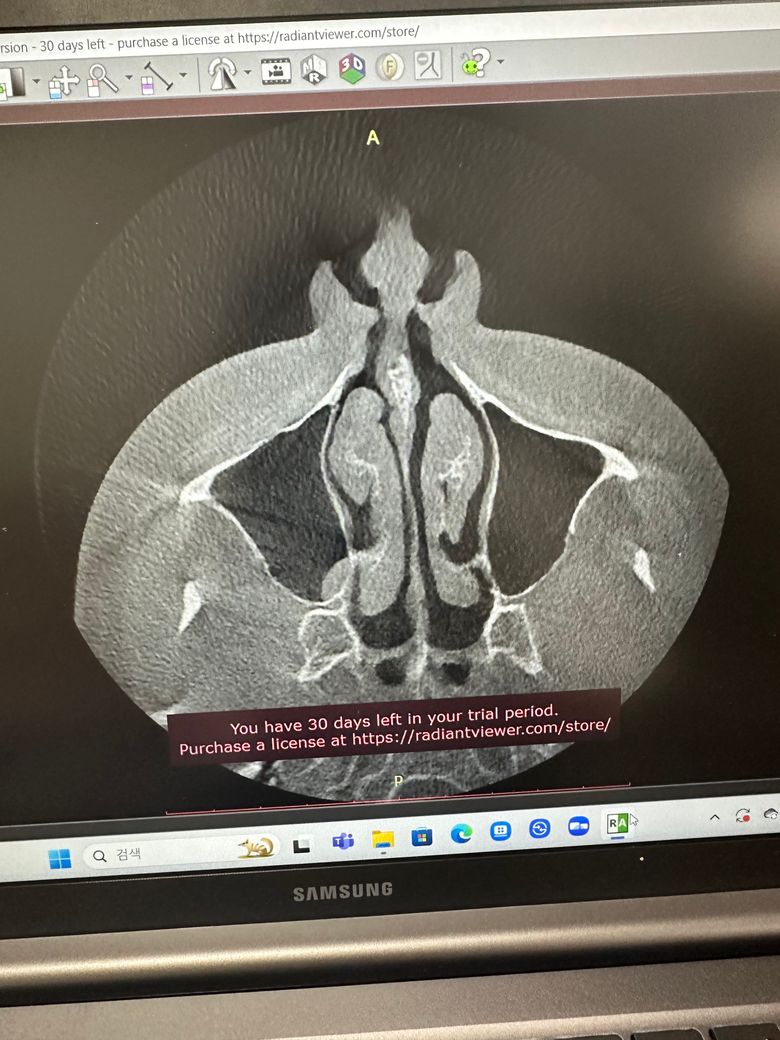

코 ct사진인데 분석 부탁드립니다!

질문 그대로 입니다 이비인후과에서 ct찍은 사진인데 ct상으로 보이는것들이랑 문제가 있다면 말씀해주시면 감사하겠습니다ㅠ

• 1번 째 사진

올리신 사진 두 컷 가지고 구체적이고 자세한 평가가 가능하지는 않습니다만, 올리신 사진 두 컷 속에는 특별히 이상 소견이 있어 보이거나 하지 않습니다.